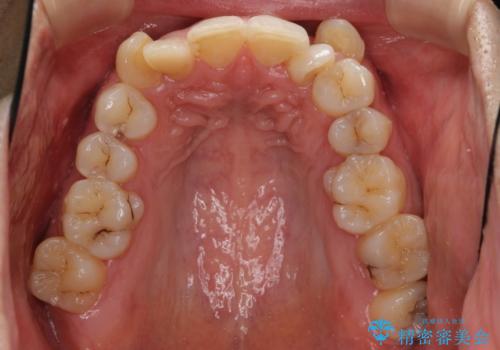

八重歯の矯正+歯のないところにインプラント

下の歯がないところに、奥歯が倒れこんでいたため、矯正治療で倒れこんだ歯を起こして、インプラントを植立しました。

- 197万円 (矯正治療95万円、インプラント治療72万円(下顎両側6)、その他補綴治療30万円(上顎両側2))費用は治療当時の料金となります

上顎の小臼歯2本、下顎の親知らずを抜歯しています。

八重歯の移動のため、矯正用ミニスクリューを使用しています。